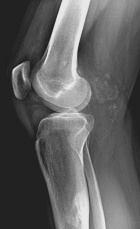

43 y/o male w 5 years of chronic R knee pain, worsening over the past 3 years. Feels like “crunching marbles”. Pain at night and worse with activity. No weight loss, fevers/chills. No systemic complaints.

PE: R knee effusion; crepitus, palpable masses near popliteal fossa, mild dec R knee ROM secondary to pain, neurovascularly intact, 5/5 motor.